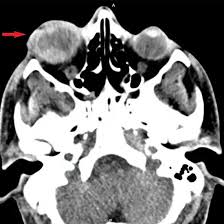

NCCT Scan Orbit Axial

An NCCT Scan Orbit Axial is a specialized test in imaging, which offers cross-sectional images of the eye socket (orbit) and its adjacent structures without using contrast dye. This is mainly used for conditions like fractures, tumors, infections, or foreign objects within the orbit. Axial ensures precise imaging in a particular plane, offering clear insights into structural abnormalities. It is a quick, non-invasive procedure that is useful for accurate diagnosis and planning for the treatment of conditions of eye and orbital health.

An NCCT scan orbit axial is used to diagnose and assess several conditions affecting the eye socket and its surrounding areas. It is often conducted for orbital fractures, tumors, infection, foreign bodies, or changes in the bones and orbits’ tissues.

This scan will determine trauma, inflammation, or any need for surgical interventions. Its excellent resolution will allow doctors to get an accurate location and nature, thus enabling strong diagnoses and treatment options in the case of most disorders concerning the eyes and their supporting structures.